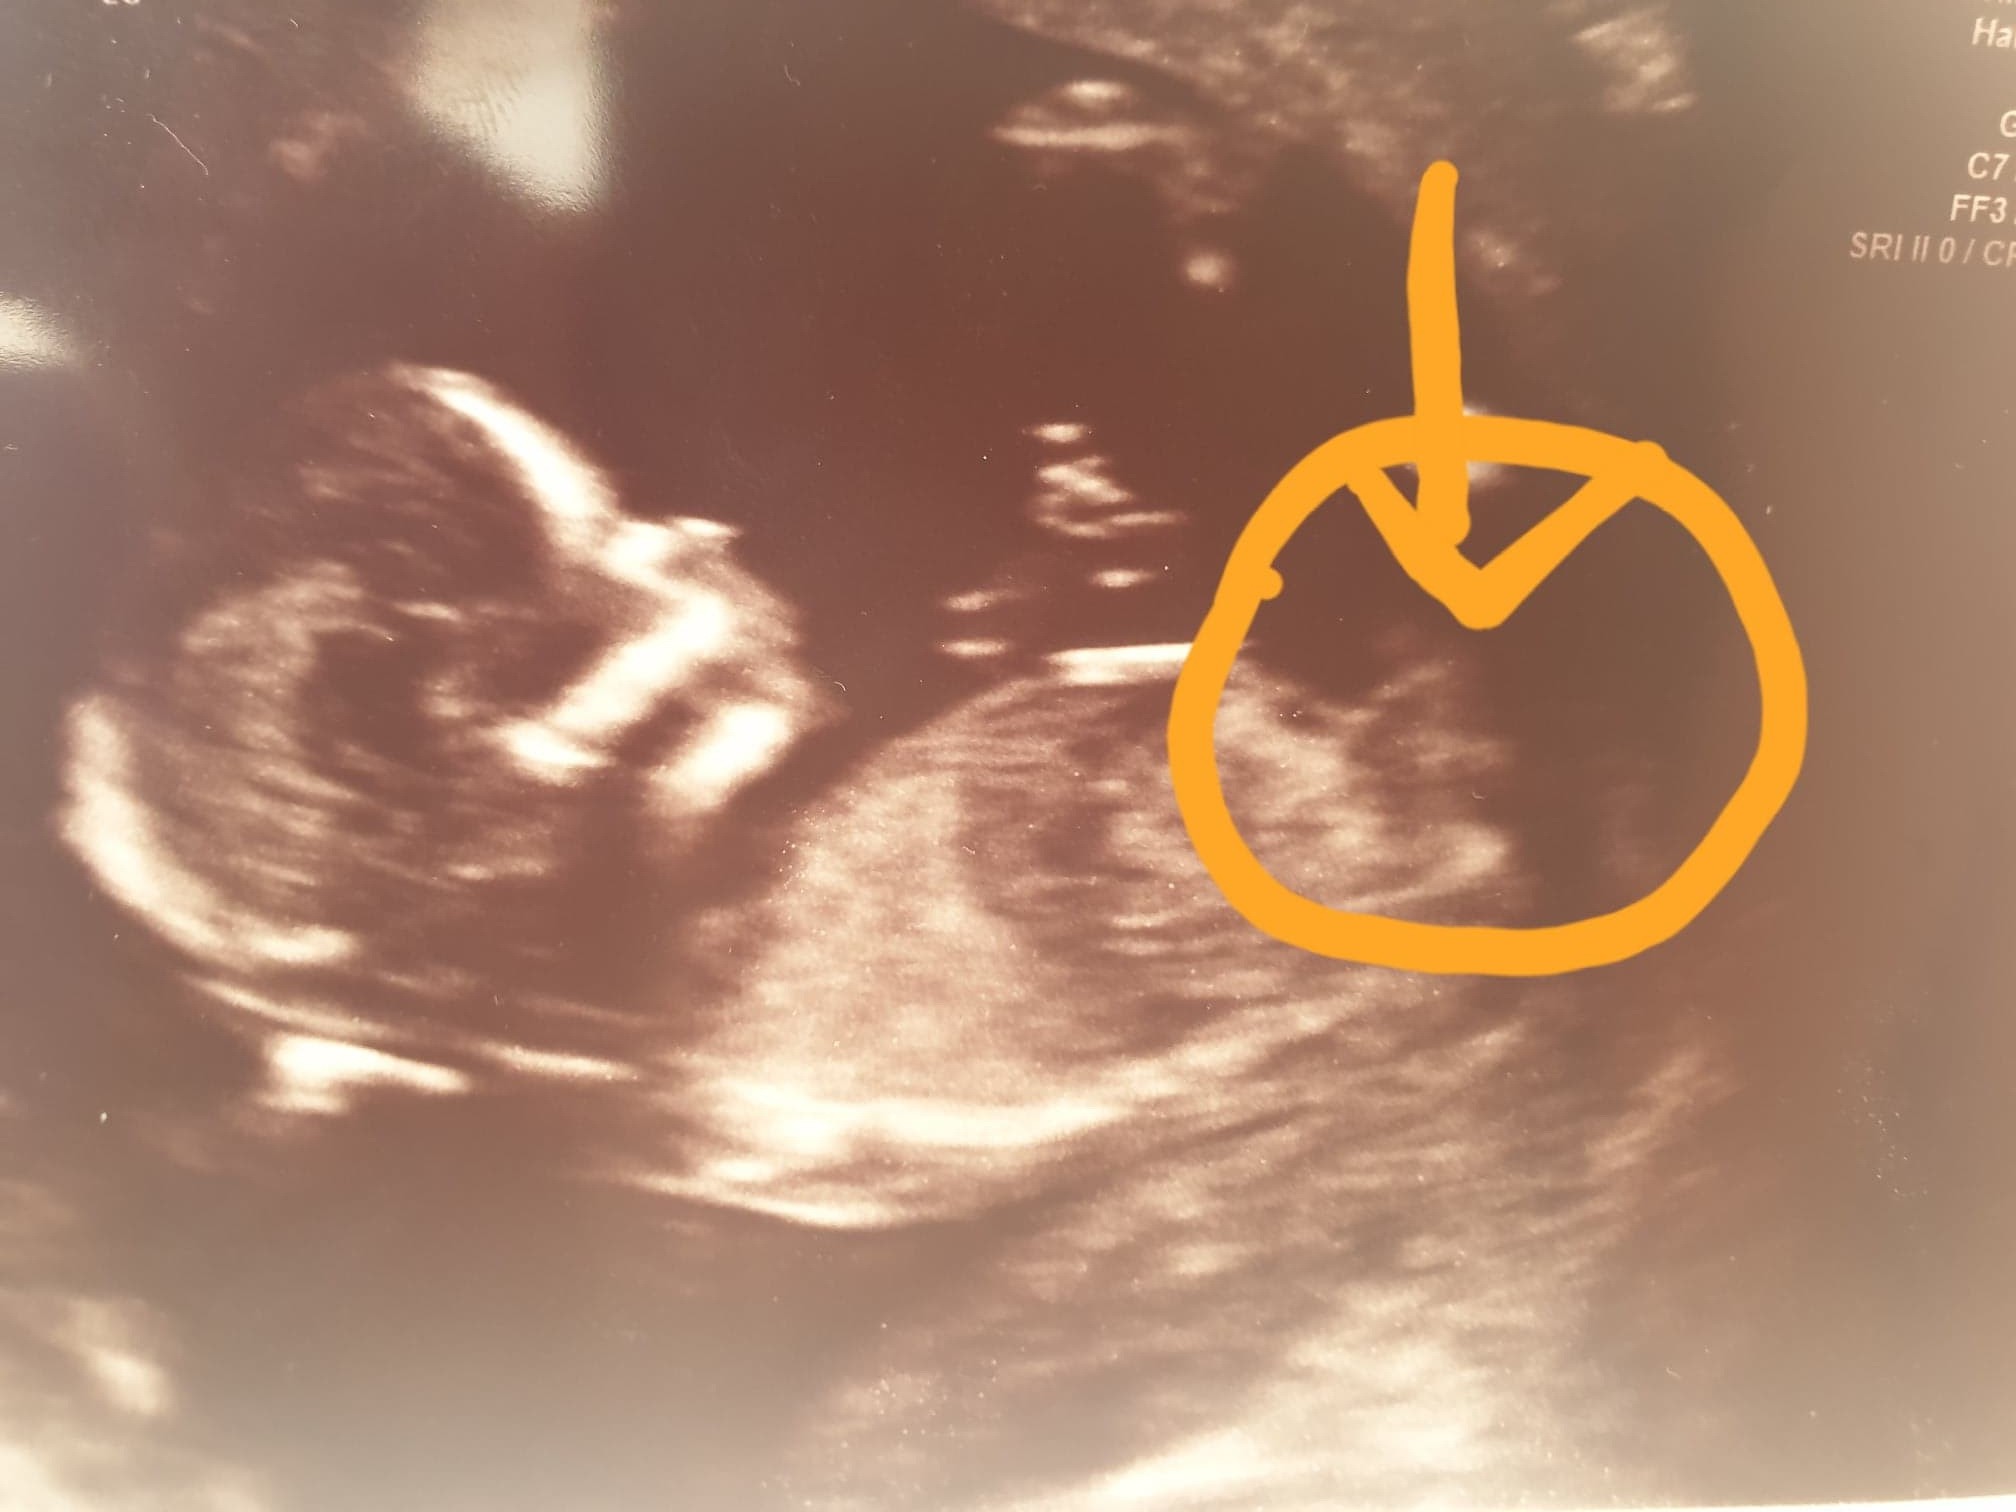

Ciężko stwierdzić. Pokaże ci moje foto z 17 tc zupełnie inne ujęcie . Z tego twojego ciężko cos obstawiać

Załączniki

• 20200128_162413.jpg

20200128_162413.jpg

1,4 MB · Wyświetleń: 1 004